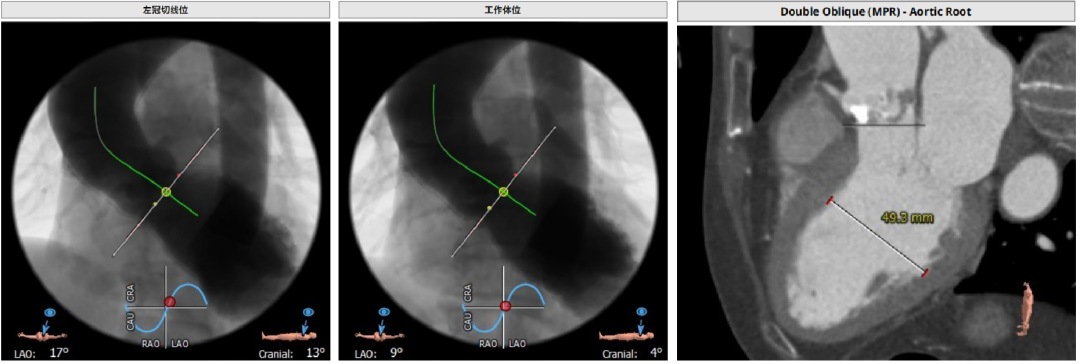

投照角度:左冠切线位球囊扩张时采用,可以观察左冠是否有冠脉风险,工作体位三窦平均拉开,无冠窦位于最低处方便瓣膜释放和定位心室大。

CT分析

Annulus:23.5,初选26/29瓣膜。LVOT短径19.3mm,STJ高度足够,宽度适中。

窦部空间足够,升主增宽,左右冠高度合适。

心脏角度不大,轻度钙化,左右窦黏粘;释放体位LAO 9、CRA 1;运用cusp-overlap技术定位角度;RAO17°、CAU 28° 。